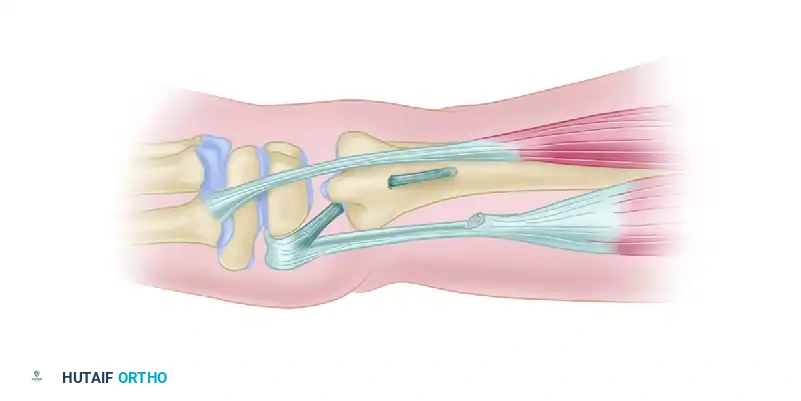

Step 2: Graft Placement and Looping

* A small tendon graft is harvested.

* The graft is looped circumferentially around the neck of the ulna to act as a neo-ligament.

Figure: An annular ligament is formed by looping the small tendon graft around the neck of the ulna and preparing it for attachment to the radius.

Step 3: Radial Attachment

* Drill holes are created in the ulnar aspect of the distal radius.

* The free ends of the tendon graft are passed through the radius to secure the ulnar loop, effectively tethering the ulna to the sigmoid notch.